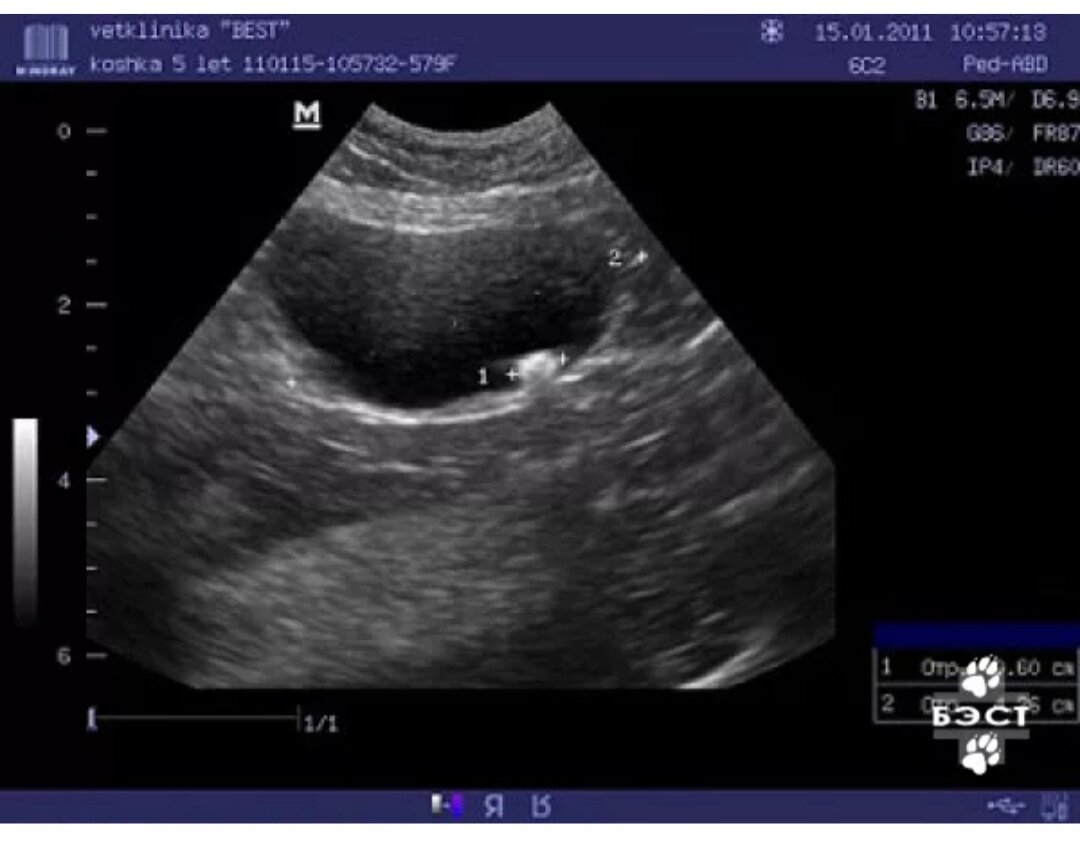

• Когда налажен отток мочи возникает возможность проведения противовоспалительной терапии. Соответственно, можно заняться и дополнительной диагностикой (анализы крови, мочи, УЗИ, рентген)

Камень в мочевом пузыре (фото из интернета)

• Пациент стабилен, мочеиспускание налажено - время для определения долгосрочной терапии, диеты. На этом этапе анализы мочи - главный способ контроля за эффективностью лечения. Первое время мочу придётся сдавать каждую неделю, далее, конечно, реже. УЗИ нужно будет делать периодически, при стабильном состоянии 1 раз в 3-6 месяцев.